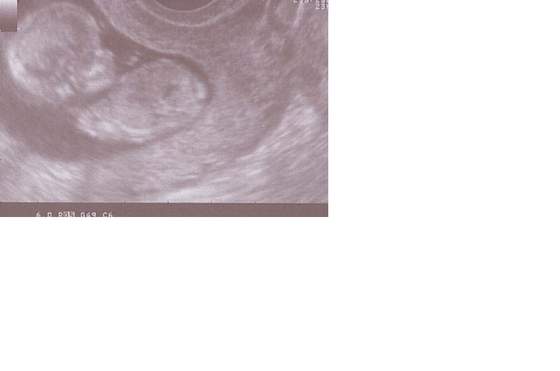

w piątek byłam na prenatalnych, z dzidziem wszystko w porządku, ma już prawie 7 cm ( nie wiem ile dokałdnie bo strasznie skakało ) termin wg tego usg wychodzi na 25.08.

KasiuP piękny maluszek a jaki ma śliczny nosek